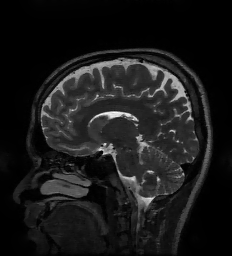

In this paper we consider solving linear inverse problems in imaging in which a -pixel image, (in vectorized form), is observed via noisy linear projections as , where and . This general model is used throughout computational imaging, from basic image restoration tasks like deblurring, super-resolution, and image inpainting [1], to a wide variety of tomographic imaging applications, including common types of magnetic resonance imaging [2], X-ray computed tomography [3], radar imaging [4], among others [5]. The task of estimating from is often referred to as image reconstruction. Classical image reconstruction methods assume some prior knowledge about such as smoothness [6], sparsity in some dictionary or basis [7, 8, 9], or other geometric properties [10, 11, 12, 13], and attempt to estimate a that is both a good fit to the observation and that also conforms to this prior knowledge. In general, a regularization function measures the lack of conformity of to this prior knowledge and is selected so that is as small as possible while still providing a good fit to the data.

Applying may be computationally prohibitive for certain large-scale inverse problems in imaging, such as those arising in CT and MRI reconstruction. To address this issue, we adapt the approach of [47] and replace all instances of in the preconditioned Neumann network by an unrolling of a fixed number of iterations of the conjugate gradient (CG) algorithm [51], which approximates the application of . Unrolling CG does not require any additional trainable parameters, and backpropagation through the CG layers can be performed via automatic differentiation. This strategy has been shown to be effective for various large-scale MRI reconstruction problems [48, 49]. Incorporating a trainable parameter into this approach is simple since the derivatives of the end-to-end network with respect to are also easily computed by automatic differentiation. In particular, we do not need to have an analytic expression in terms of in order to compute derivatives.

5.6 MRI Experiments

| Original/Mask | PNN | NN | MoDL | GDN2 | GDN1 | TNRD | TV |

| PSNR (dB) | 34.95 dB | 33.09 dB | 34.09 dB | 33.18 dB | 31.37 dB | 32.39 dB | 32.29 dB |

| Test Time (sec) | 16.3 sec | 5.5 sec | 14.3 sec | 5.7 sec | 3.1 sec | 4.0 sec | 349.2 sec |

In this section we provide results of multi-coil MRI reconstruction from undersampled measurements. Full training and test data is the data used for the experiments in [47], consisting of 12-coil Cartesian sampled k-space data of dimension with known coil sensitivity maps. The size of the training set is 360 such acquisitions across 4 subjects, with testing being performed on 40 images from one, separate subject who was not used for training. The sum-of-squares reconstruction is treated as ground truth. Further details of the data acquisition can be found in [47].

All experiments are for 4 undersampling, although we differ from [47] in that we train on a fixed k-space undersampling mask. The undersampling mask is fully sampled in the center 0.15 fraction of frequencies, with the remaining frequencies being sampled according to a random Gaussian pattern. The mask is visualized in figure 10.

For the MRI experiments we follow the precedent set by [47] in our choice of learned component, using only a simple five-layer convolutional network with 64 filters per layer and ReLU nonlinearities for all architectures other than TNRD. The TNRD architecture follows the architecture proposed in [33]. The Neumann network results presented here are for the preconditioned Neumann network (PNN), and the number of blocks for GDN, PNN, MoDL, and TNRD is fixed to be 5. The preconditioning operator in PNN is implemented through 10 conjugate gradient iterations, identically to [47]. We compare to GDN with the same initialization as NN (GDN1) and as PNN (GDN2) to study the effect of different initializations on GDN.

We observe that unrolled optimization approaches are advantageous in this setting compared to the more traditional TV-regularized reconstruction. Preconditioning, both to improve initialization as in GDN2, and incorporated into the architectures, as in PNN and MoDL, improves PSNR significantly in this setting.

A major benefit of learned reconstruction methods is their test time, which is displayed beneath the method name and PSNR in Figure 10. We note that all learned approaches reconstruct an order of magnitude faster than the agnostic TV approach. Although preconditioning incurs an additional cost in terms of test time, the performance increase is substantial for MoDL and PNN.